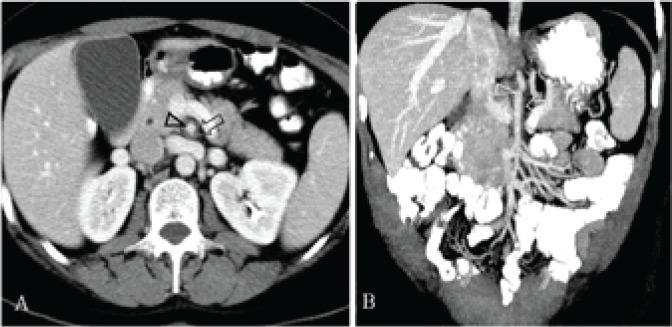

Her vital signs were normal. Abdominal examination revealed tenderness to deep palpation in the epigastrium, without guarding or rebound. The remainder of the clinical examination, including skin and nervous system, was unremarkable. Laboratory tests showed lymphopenia (1,000/μL) and mild anemia (13.6 g/dL). The rest of the blood tests, including liver enzymes and serum and urine amylase, were within normal range. A chest radiograph was normal. Abdominal computed tomography (CT) reported periarterial fat stranding and possible dissection of the superior mesenteric artery (SMA) (Figure 1) and the patient was transferred to our hospital for further evaluation and treatment.

Figure 1.

CT scan following intravenous contrast administration, split-bolus excretory-portal phase. (A) Axial slice shows the superior mesenteric artery containing a hypoenhancing line (arrowhead) and surrounded by perivascular fat stranding (arrow). (B) Coronal reconstruction shows a short line at the upper aspect of the lumen (arrowhead) and thickening of the adjacent wall (arrow). Findings were initially interpreted as dissection.